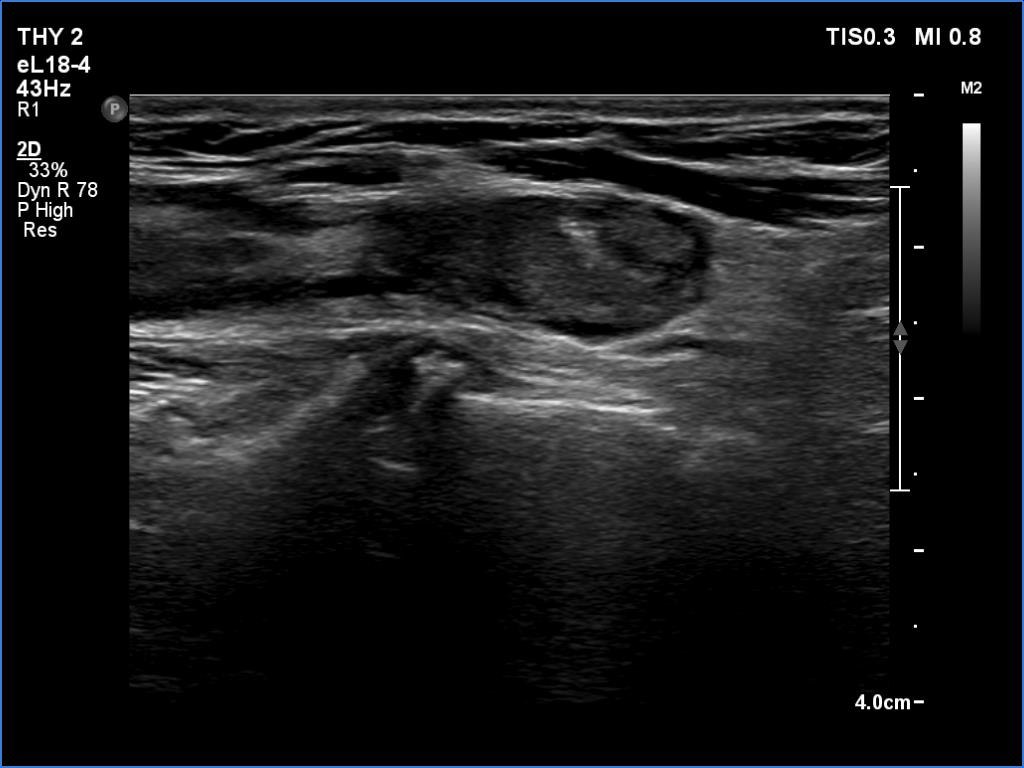

First examination (first row of images):

Clinical data: A 61-year-old woman was referred for evaluation of a suspicious recurrent nodule which was discovered on carotid Doppler examination. The patient was operated on Graves' disease 17 years ago. Histopathology disclosed diffuse goiter.

Palpation: no abnormality.

Laboratory tests: TSH 3.09 mIU/L on daily 75 microgram levothyroxine.

Ultrasonography. There was a small, moderately hypoechoic remnant according to the resected right lobe while a much larger but still small remnant was found in the left thyroid bed. The latter had an amorphous discrete lesion which presented bright echogenic granules. The lesion was avascular.

FNA was performed from the mass. There were no follicular cells on the smear, only inflammatory cells were found. Our diagnosis was granulation around surgical thread.